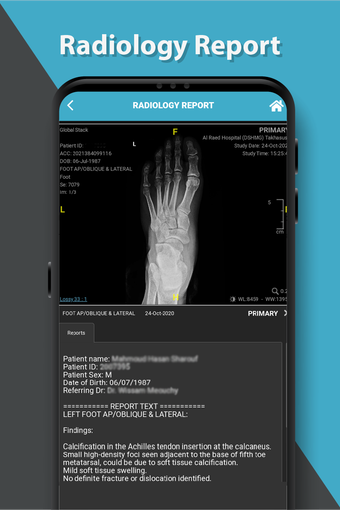

これは、Dr. Sulaiman Al-Habib Medical Services Groupが提供するすべてのサービスにアクセスするのを助ける無料のアプリです。グループの持続的なデジタル変革の重要な部分であり、効率と生産性の向上を重視しています。この新しいアプリは、オンライン医師相談から医療検査や放射線学の報告書まで、グループが提供するすべてのサービスに簡単にアクセスできるようになります。また、あなたと家族の医療記録を閲覧する機会も提供しています。